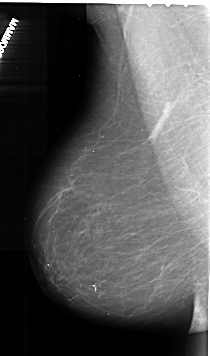

A_1010_1.LEFT_MLO

LEFT_MLO LINES 6046 PIXELS_PER_LINE 3556 BITS_PER_PIXEL 16 RESOLUTION 42 NON_OVERLAY